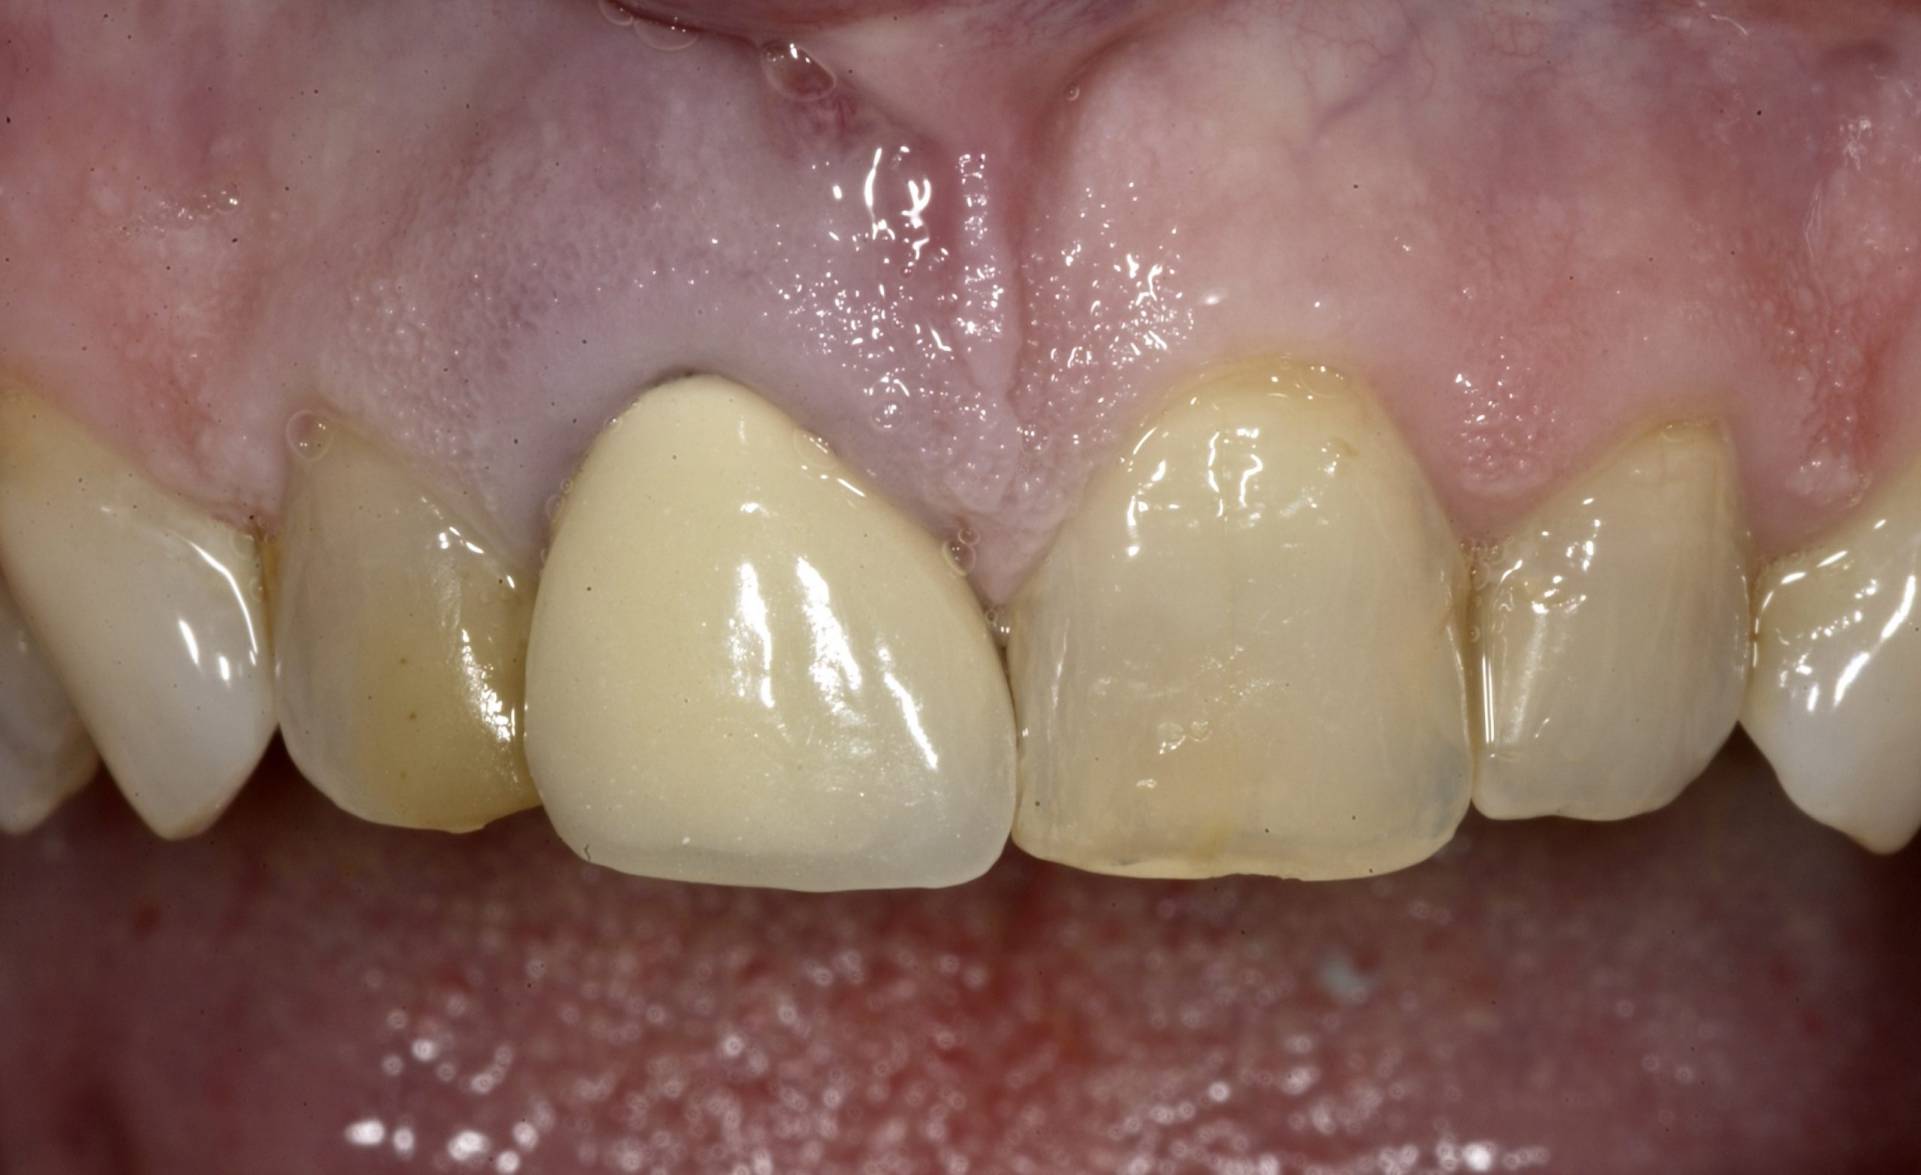

Das Ziel ist eine funktionell und ästhetisch perfekte Versorgung, die sich harmonisch in das bestehende Gebiss einfügt – für langfristige Stabilität, Sicherheit und ein natürliches Gefühl beim Kauen und Sprechen.